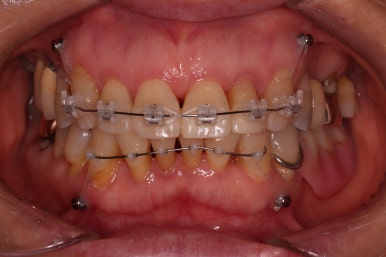

마무리 때의 사진입니다.

교정치료 자체는 9개월만에 끝냈지만 잇몸이 약해서 재발이 우려됐고 예후가 불량해서 뽑아야 되는 치아도 있어 해당 부분을 임플란트를 할 지 최대한 계속 써볼지 등에서 고민하느라 최종 종료는 한참 더 걸리긴 했어요.

부착형 유지장치 뿐만 아니라 보조적으로 재발을 막아줄 목적의 독특한 형태의 뺐다꼈다 유지장치도 드렸어요.(여기서는 공개 안할겁니다. 비밀입니다. ㅎㅎ)

부산부분교정 전후사진을 비교해 볼게요.

치열이 매우 가지런해졌고 보이던 틈새도 다 없어졌으며 뻐드러진 느낌도 완벽히 좋아졌어요.

잇몸에서 쑤욱 빠져나와 보이던 치아도 원위치를 찾았고요.

앞니도 약간이나마 뒤로 들어가서 입매도 많이 좋아졌어요.